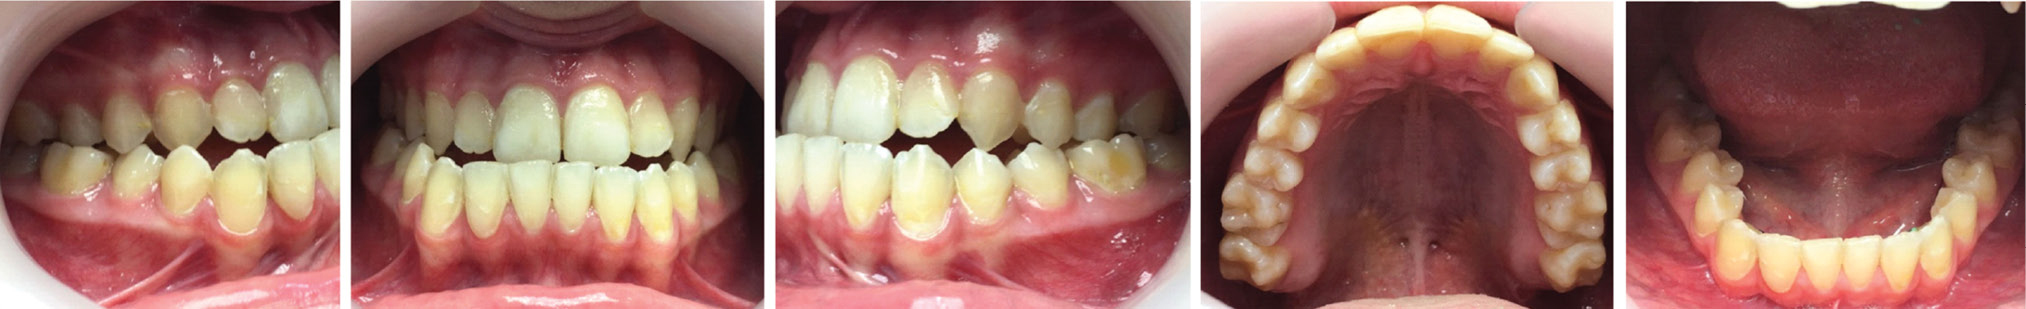

После проведения клинического обследования и антропометрии гипсовых моделей челюстей выявлено соотношение зубных рядов по III классу Энгля (мезиальная окклюзия) (рисунок 2), правильные форма и размеры зубных дуг верхней и нижней челюстей.

Рисунок 2. Смыкание зубных рядов (слева, спереди, справа), верхний и нижний зубные ряды пациентки Т., 18 лет, с мезиальной окклюзией гнатической формы до операции на нижней челюсти.

Через 6 месяцев после операции были сделаны повторные исследования (рисунки 6–9).

Рисунок 7. Смыкание зубных рядов (слева, спереди, справа), верхний и нижний зубные ряды пациентки Т., 18 лет, с мезиальной окклюзией гнатической формы после операции.